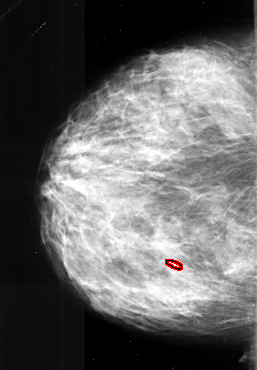

A_1031_1.LEFT_MLO

FILE: A_1031_1.LEFT_MLO.OVERLAY

TOTAL_ABNORMALITIES 1

ABNORMALITY 1

LESION_TYPE CALCIFICATION TYPE PLEOMORPHIC DISTRIBUTION LINEAR

ASSESSMENT 4

SUBTLETY 1

PATHOLOGY MALIGNANT

TOTAL_OUTLINES 1

BOUNDARY